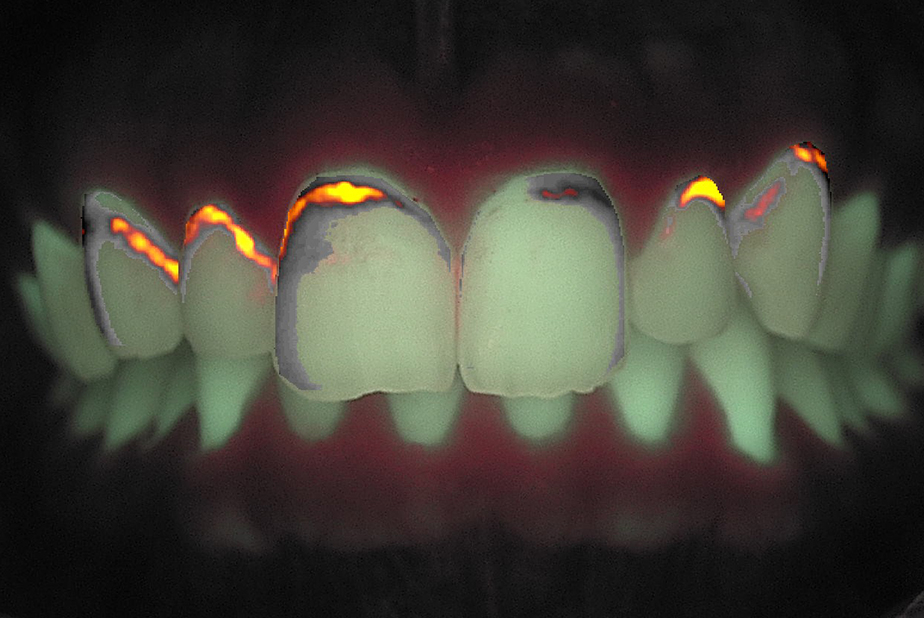

obiettivo in luce bianca si osservano white spot a livello degli elementi 11, 12, 21 e 22. L’esame in fluorescenza con QrayCam Pro conferma la presenza di zone a ridotta mineralizzazione con perdita di fluorescenza compresa tra –47,8% e –56,1% e area di white spot fino a 4007 px².

Fig. 1B - Fluorescenza pretrattamento. Valori ΔF medi intorno a –47,8%, indicativi di demineralizzazione.